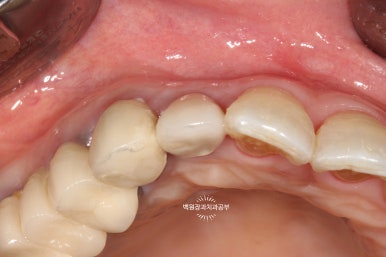

치아를 약간 정출시킨 후 봉합사를 이용하여 고정해줍니다.

보시는 바와 같이 치아를 약간 정출시켜줍니다. 대개는 2-3mm 정도 정출시킵니다.

그렇기 때문에 뿌리가 너무 짧은 치아는 이러한 외과적 정출술이 불가능합니다.

오른쪽 사진을 보시면, 입천장 쪽에서 보았을 때 치아가 보다 더 정출한 것을 보실 수 있어요.